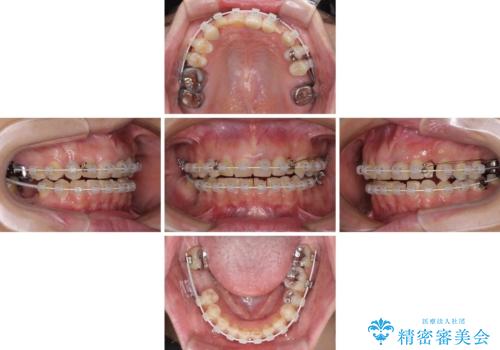

咬み合わせ改善のため、前歯の過剰歯を抜去し、ワイヤー矯正にて歯列と咬み合わせることとしました。

左上の奥歯のブリッジや前歯のセラミッククラウンはいったん除去し、矯正治療後に補綴治療を行うこととしました。

また、右下の抜歯が必要な奥歯は、矯正治療の途中でインプラントを埋入し、矯正治療後に上顎と合わせて補綴治療を行うこととしました。

上下非接触の咬み合わせは、舌突出癖によるところが大きく、トレーニングを行いながら治療を進めていきました。

なかなか突出癖が改善できず、過剰歯を抜歯したスペースを閉じるまでに時間がかかりました。

舌突出癖の改善は、治療期間や仕上がりに大きな影響を与えるため、しっかりとトレーニングすることが大切です。